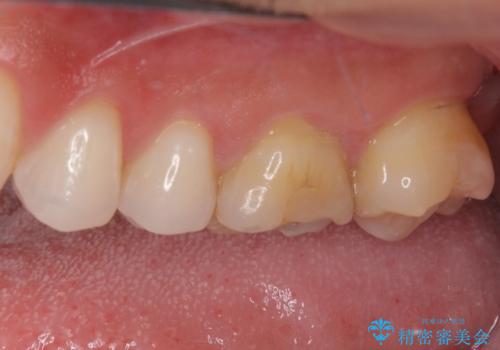

- 奥歯の詰め物が外れてしまったとのことで来院された患者様です。

幾度も詰め物治療を行ったため継ぎ接ぎだらけとなっていたため、インレーにて修復治療をすることとしました。

咬合力が強いため、ゴールド合金(PGA)のインレーを選択することとしました。